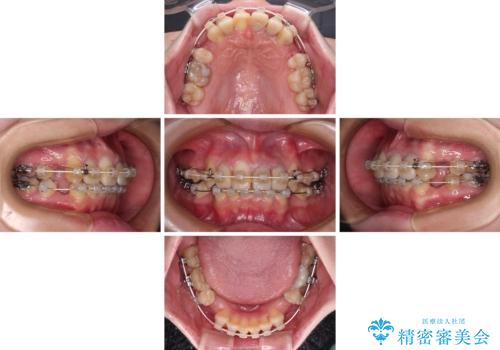

- 前歯のデコボコと、その結果むし歯が進行していることを気にして来院された患者様です。

前歯や奥歯の根管治療を行い、その後上下左右の第一小臼歯4本を抜歯してワイヤー装置にて矯正治療を行うこととしました。

矯正治療後には、根管治療を行った歯をオールセラミッククラウンにて補綴治療を行うこととしました。

治療途中で激務の会社に就職することとなり、なかなか矯正治療に通院することができなくなり、治療期間が想定の2倍近くとなりましたが、無事に満足のいく形で治療を終えることができました。